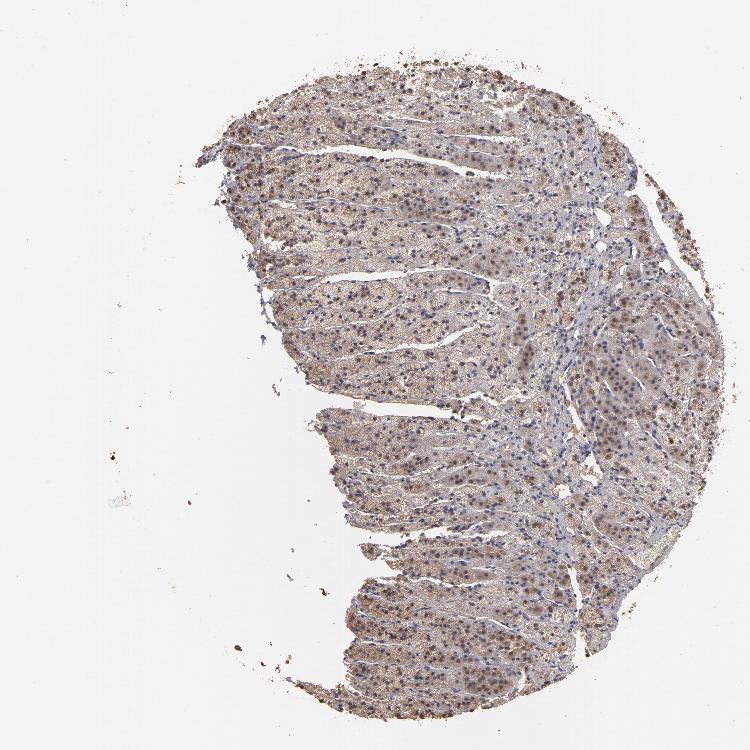

ADRENAL GLAND - Antibody stainingi

Antibody staining in the annotated cell types in the current human tissue is reported as not detected, low, medium, or high, based on conventional immunohistochemistry profiling in selected tissues. This score is based on the combination of the staining intensity and fraction of stained cells.

Each image is clickable and will lead to virtual microscopy that enables deeper exploration of all samples and also displays staining intensity scores, fraction scores and subcellular localization as well as patient and tissue information for each sample.

Antibody HPA002835

Glandular cells Medium